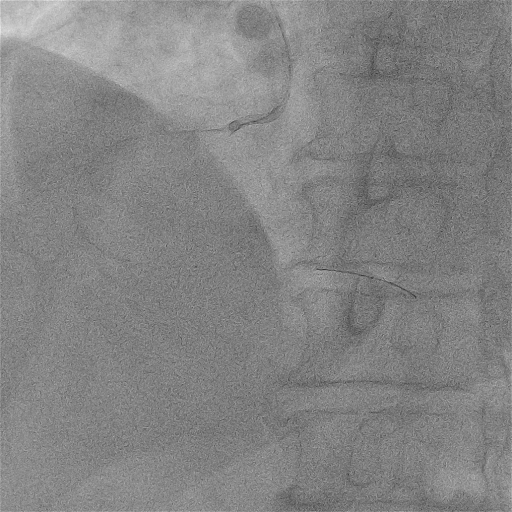

外院RCA冠脉造影和PCI

造影显示右冠全程弥漫多处95%以上狭窄伴重度钙化,最重处次全闭塞,CTO导丝通过病变后,球囊及ELCA导管均无法通过,未能完成PCI治疗。